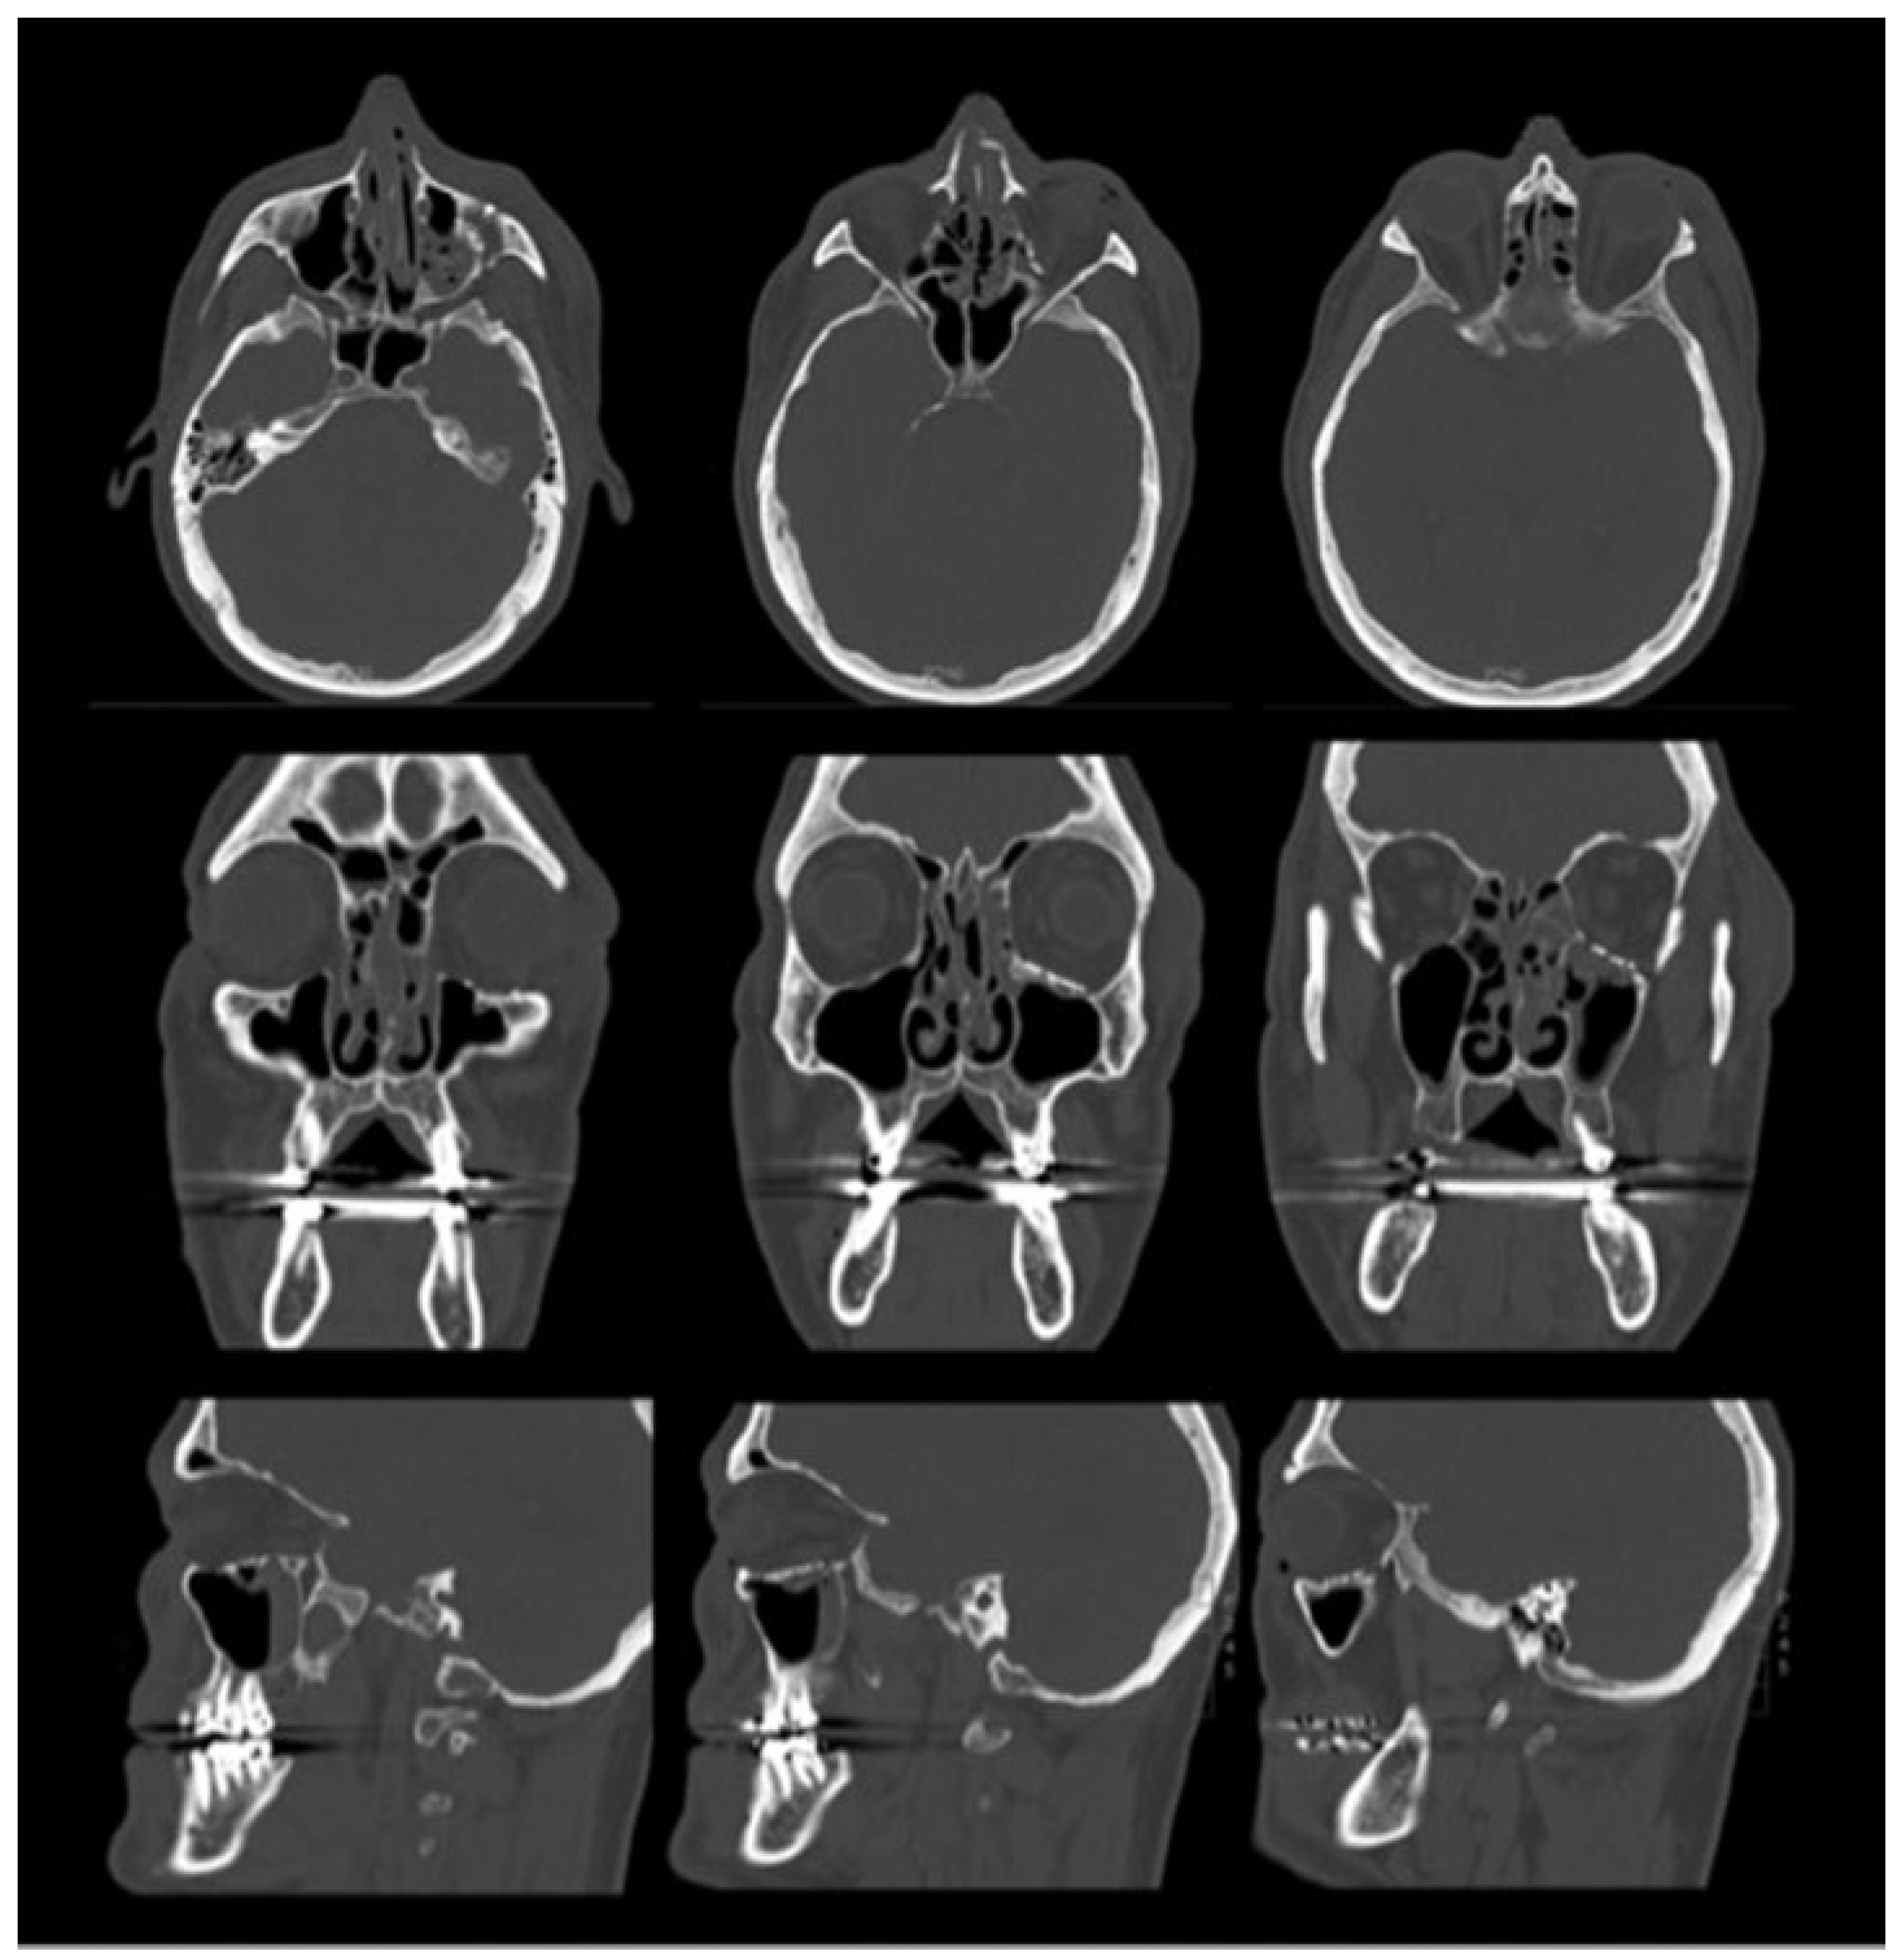

The patient was subsequently extubated and visual acuity was noted to be intact, with pupillary light response present before leaving the operating room. A maxillofacial CT was performed immediately postoperatively and demonstrated reconstitution of the orbital volume, with adequate placement of the hardware and no evidence of retrobulbar hemorrhage or impingement of the orbital apex by the hardware (Figure 3). Of note, there were no documented episodes of hypo- or hypertension intraoperatively.

Figure 3. Immediate postoperative computed tomography. Axial (top row), coronal (middle row), and sagittal (bottom row) images show reconstruction of the orbital floor with a titanium mesh implant. The orbital volume is almost fully restored. There is no evidence of impingement of the hardware on the optic canal and no retrobulbar hemorrhage.